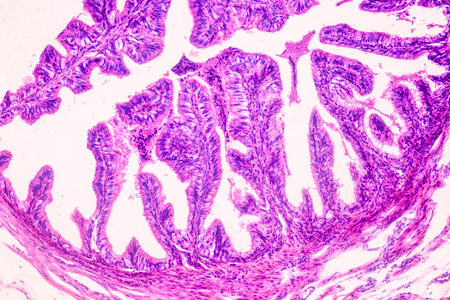

Bowen's Disease Tumor under the microscope 100x

Bowen's Disease Tumor under the microscope 100x